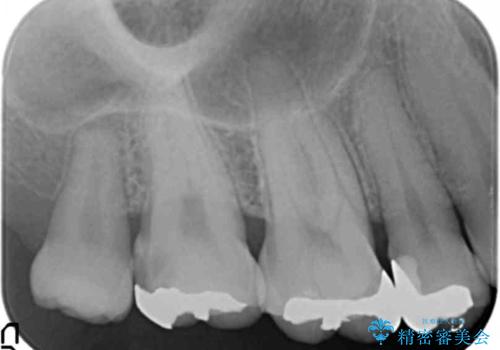

食べ物が詰まる 親知らずが原因の虫歯再発

- 銀歯と親知らずの間に毎回食べ物が挟まることを自覚していたが、放置した結果虫歯が再発し検診で発覚し治療を行うこととなりました。

原因となる親知らずや周囲の虫歯は、出産後に行う予定です。